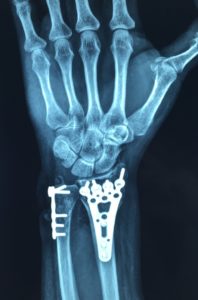

El tratamiento quirúrgico consiste en realizar una intervención para reducir manualmente o con instrumentos la luxación o subluxación, y fijarla mediante tornillos, alambres o placas. También se puede realizar una osteotomía, que es un corte y remodelación del hueso para mejorar el ajuste entre el acetábulo y la cabeza femoral. El tratamiento quirúrgico se reserva para los casos más severos o que no responden al tratamiento conservador.